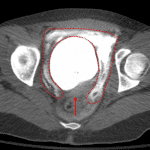

- Wall thickening of the anterosuperior bladder with a possible focal defect and adjacent small amount of low density free intraperitoneal fluid layering dependently in the pelvis

- Defect in the anterosuperior bladder with contrast spillage into the peritoneal cavity, layering dependently in the pelvis

- Intraperitoneal bladder rupture

Findings concerning for intraperitoneal bladder with a likely focal defect along the anterosuperior bladder wall. Recommend CT cystogram for further evaluation.

Intraperitoneal bladder rupture with a defect in the anterosuperior bladder wall.